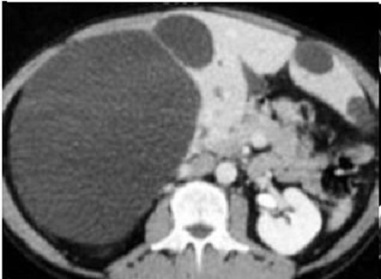

Image de kytes

multiple tres volumineuse du foie droit et a lobe gauche du

foie. Ce sont des image ovalaire hypodensite a

bord tres nette , bien limite situe au foie droit |

Aspect TDM une

kyste du foie droit avec image de calcifie

de sa paroi . En cas hemorragie

intrakystique on peut en voyait image de cailleaux

hyperdense du sang |